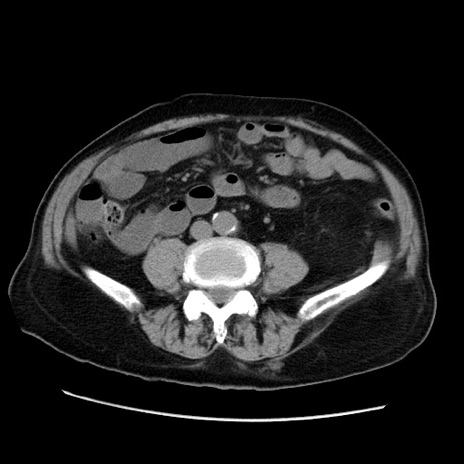

症例21(横断像)

【症例】70歳代男性

【主訴】腹痛

【現病歴】肝硬変・肝細胞癌にてかかりつけの方。約9時間前に食後より腹痛出現。症状が徐々に増悪し、嘔吐出現したため来院。

【既往歴】肝硬変、肝細胞癌(RFA、TACE後)

【身体所見】意識清明、表情苦悶様、BT 36℃、BP 129/78mmHg、P 88bpm、SpO2 97%(RA)、右上腹部から心窩部にかけて圧痛あり、反跳痛なし、筋性防御あり。

【データ】WBC 5800、CRP 0.16